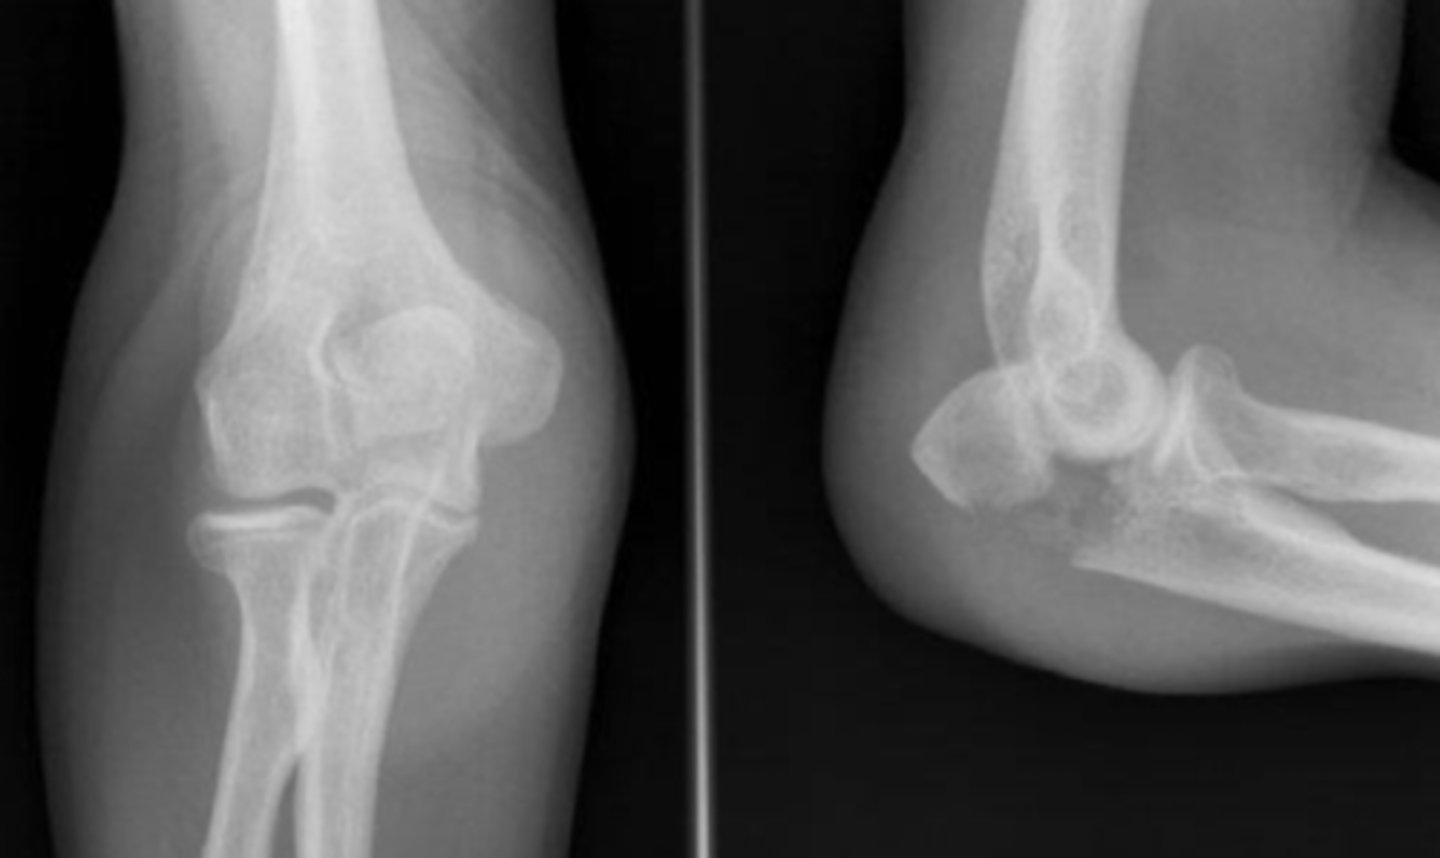

Lateral elbow

What view does this show?